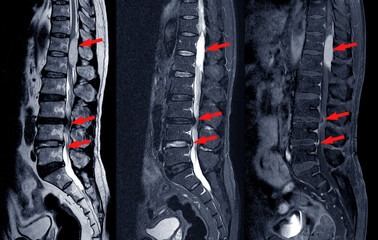

脊柱管狭窄症(せきちゅうかんきょうさくしょう)とは、脊柱管(せきちゅうかん)という背骨の中にある神経の通り道が狭くなる状態を指します。脊柱管には脊髄や神経根が通っており、これが圧迫されることで痛みやしびれなどの症状が現れることがあります。

脊柱管狭窄症とは?